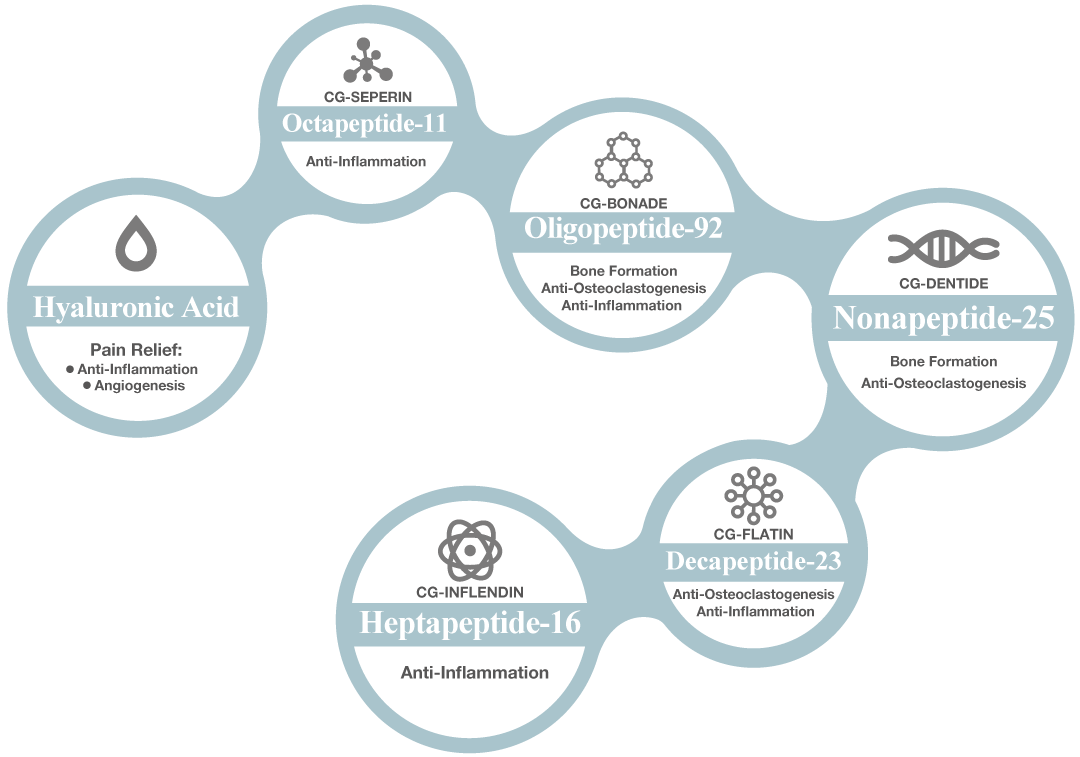

Biomimetic Matrix Peptides Specific in OA

OCTAPEPTIDES – CG SEPERIN

Octapeptides reducing the production of cytokines (IL-17, IL-23, IL-6 and TNF-α) and chemokines monocyte chemoattractant protein 1 in the joints of arthritic or in synovial cell culture supernatant, and increased the levels of IFN-γ and TGF-β.

- Is effective in suppressing both inflammatory and Th17 responses in CIA.

- Represent a new therapeutic modality for rheumatoid arthritis. (4)

OLIGOPEPTIDES – CG BONADE

- BONE FORMATION: The results suggest that acidic oligopeptide is useful for drug delivery to bone and E2-(L-Asp)6 is a good candidate as an anti-osteoporosis drug without the adverse side effects of E2. (5)

- ANTI-OSTEOCLASTOGENESIS: The shTACE/peptide carrier complex alleviate arthritic symptoms in collagen induced arthritis (CIA) models by demonstrating enhanced anti-inflammatory and anti-osteoclastogenic effects. (6)

- ANTI-INFLAMMATORY: This peptide inhibits the biological activities of IL-6 in vitro and in vivo. This approach is an interesting development among other strategies aimed at targeting IL-6 in inflammatory diseases. (7)

NONAPEPTIDES – CG DENTIDE

- BONE FORMATION: this peptide in binding to transmembrane proteins to promote intracellular events leading to cell functions. It promote bone formation without any recognizable antigenic activity. Its potential application value for regenerative medicine, especially for bone tissue engineering. (8)

- ANTI-OSTEOCLASTOGENESIS: Receptor activator of nuclear factor-κB (RANK) and RANK ligand play a pivotal role in bone metabolism, and selective targeting of RANK signaling has become a promising therapeutic strategy in the management of resorptive bone diseases. Nonapeptides is a small peptide inhibitors specifically targeting the receptor RANK and it is new therapeutic opportunity for the treatment of resorptive bone-disease. (9)

DECAPEPTIDES – CG FLATIN

- ANTI-INFLAMMATORY: the decapeptide is a potent anti‐inflammatory peptide that has potential therapeutic applications, especially for PLA2‐ in synovial fluid from patients with RA inflammatory arthritis. (10)

- ANTI-OSTEOCLASTOGENESIS: Activate the proliferation of type II collagen specific T cell response and antibody formation in rheumatoid arthritis (RA) and their relations to HLA-DR4 subtype. (11)

HEPTAPEPTIDE – CG INFLENDIN

- ANTI-INFLAMMATORY: the RGD peptide (RGD-4C) was covalently linked to a proapoptotic heptapeptide binds selectively to the αvβ3 and αvβ5 integrins accumulated in inflamed synovium but not in normal synovium. Homing of RGD-4C phage to inflamed synovium was inhibited by co-administration of soluble RGD-4C. Intravenous injections of the RGD-4C–D(KLAKLAK) 2chimeric peptide significantly decreased clinical arthritis and increased apoptosis of synovial blood vessels, whereas treatment with vehicle or uncoupled mixture of the RGD-4C and the untargeted proapoptotic peptide had no effect. Targeted apoptosis of synovial neovasculature caninduce apoptosis and suppress clinical arthritis. This form of therapy has potential utility in the treatment of inflammatory arthritis. (12)